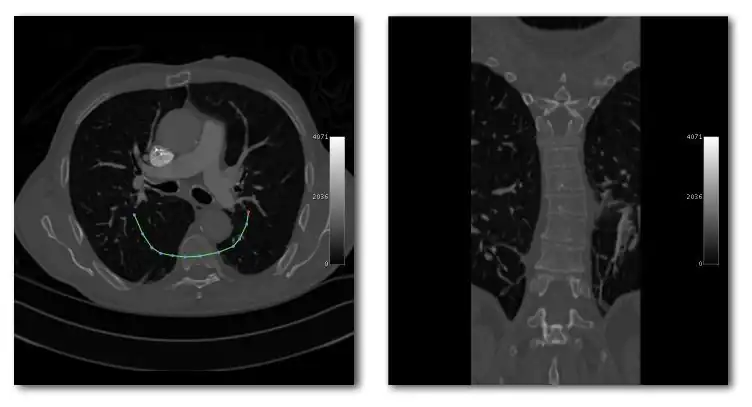

We'll conclude this chapter by considering an application of 3D visualization which integrates many of the image processing techniques we've described in this wikibook. We'll use the two SPECT scans, from a patient's lung-ventilation (V) and lung-perfusion (Q) studies, in an attempt to visualize any mismatch(es) characteristic of pulmonary embolism (PE). The application we'll consider is called subFusion Processing because it involves both image subtraction and image fusion techniques.

Note again that the SPECT studies were generated using a swamping technique where the perfusion scan was acquired immediately following the ventilation scan using an administered activity which generated a relative count rate of about 5:1 between scans. The first image processing step therefore is to correct the perfusion scan for the background ventilation activity.

Since the ventilation tracer in this case was administered using a aerosol, we can assume for simplicity that its biodistribution is reasonably identical in the two scans. Further, since the scans were acquired about 15 minutes apart using the 99mTc radioisotope, we can assume a negligible effect from radioactive decay. We can simply therefore subtract the ventilation stack from the perfusion stack, on the basis of these assumptions, to isolate what we'll call the "pure perfusion" scan.

The second step is to normalize the two scans by multiplying the ventilation stack by a factor such that the mean counts (for example) in the two stacks are similar.

Since a PE mismatch is likely to arise from regions of the lungs which contain counts in the ventilation scan and are relatively bereft of such counts in the perfusion scan, we can subtract the "pure perfusion" stack from the ventilation stack, as a third image processing step, to isolate any such differences as positively-valued features.

The final image processing step is to volume render this difference stack along with the "pure perfusion" scan and to blend the results, as illustrated in the following image:

The steps involved are outlined in the following diagram. Note that minor processes, such as CLUT selection, relative opacity adjustment and contrast enhancement are omitted from this diagram for the sake of simplicity. Note also that an image registration step may need inclusion at the beginning of the procedure in cases where patient movement occurs between the two SPECT acquisitions.